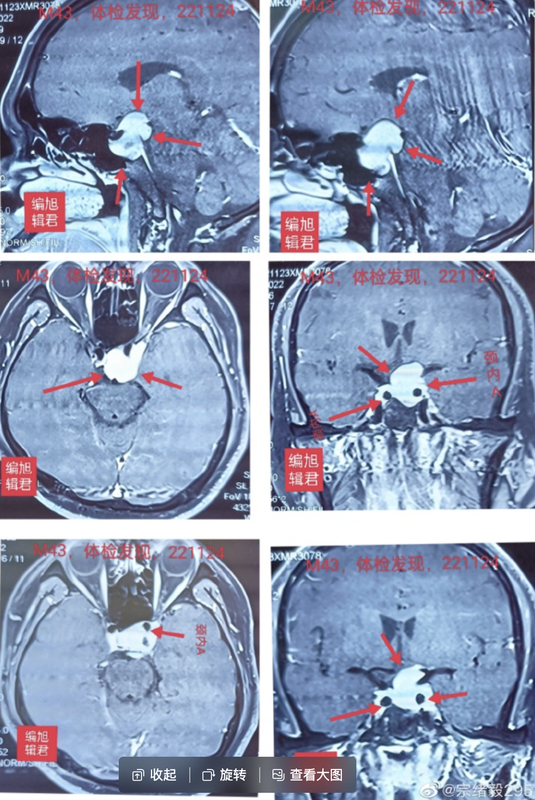

一、分享一個極高泌乳素血癥垂體腺瘤病案。某患者43歲,體檢發(fā)現(xiàn)顱內(nèi)腫瘤,考慮為垂體腺瘤,向顱內(nèi)分葉狀生長,侵襲海綿竇,左側(cè)為主,包繞頸內(nèi)動脈;檢查激素發(fā)現(xiàn)泌乳素【PRL】極高62057(86-324),比正常值上限高大191.5倍。而無任何不適。二、關(guān)于此病的治療分為兩種意見:1、先手術(shù)盡可能切除,再輔以藥物治療,避免先服藥,腫瘤質(zhì)地變韌,效果不佳時,切除困難。2、應當先服藥治療,此泌乳素極高,臨床上,一般認為大于100倍以上,藥物治療效果良好。再手術(shù)對侵襲性垂體腺瘤,很難切除完美,且有風險。三、求診于旭君,問我何建議?建議先服藥。因泌乳素越高對藥物越敏感,如此高的泌乳素,近200倍,且侵襲海綿竇,包繞頸內(nèi)動脈,分葉不規(guī)則生長,很難有效切除。服藥從小量開始,每月檢查血泌乳素,隨時調(diào)整用藥量。祝福病患早日康復。